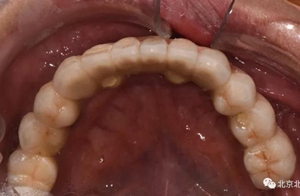

圖十四:口內(nèi)照

圖二十:永久修復(fù)咬合關(guān)系

圖二十五:口內(nèi)照。